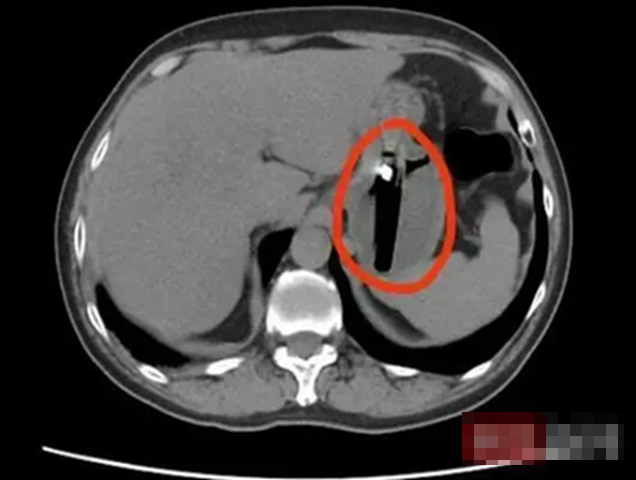

Kết quả chụp CT khiến cả bệnh nhân lẫn bác sĩ bất ngờ: trong dạ dày của anh có một dị vật dài khoảng 8cm. Sau khi khai thác kỹ tiền sử, bác sĩ nghi ngờ dị vật này chính là một chiếc bật lửa mà bệnh nhân đã vô tình nuốt phải trong một lần say rượu cách đó khoảng một tháng.

Do nguy cơ cao, các bác sĩ quyết định phẫu thuật khẩn cấp. Vì dị vật lớn, hình dạng không đều và chứa khí dễ cháy, việc gắp thông thường tiềm ẩn rủi ro. Dưới sự chỉ đạo của trưởng khoa, ê-kíp đã sáng tạo sử dụng găng tay y tế chuyên dụng để bao bọc và lấy trọn chiếc bật lửa ra ngoài, tránh gây tổn thương thêm cho thực quản và dạ dày.